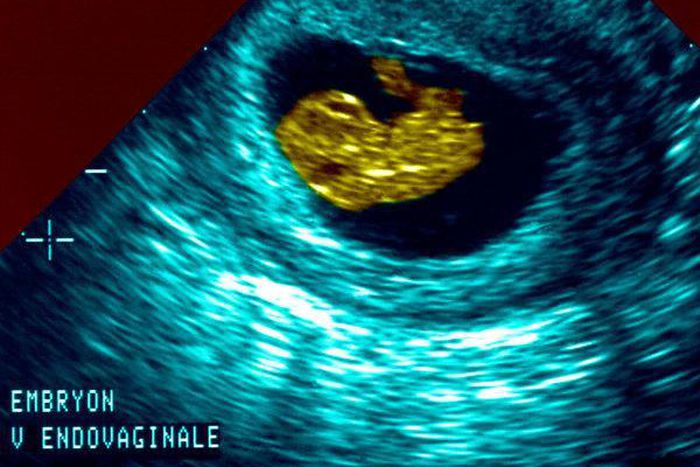

These so-called “heartbeat” laws ban abortion after the point when a fetal heartbeat can be detected. This often occurs as early as six weeks into a pregnancy, when an ultrasound may be able to detect the pulsing of what will become the fetus’ heart.

At six weeks into a pregnancy, the tissues that will become the heart are beginning to develop and a pulsing can be detected that is faster than the heartbeat of the expectant mother.

Several medical experts, including those opposed to the new abortion restrictions, say that it isn’t medically correct to call that pulsing a heartbeat. Rather, they say, it is the vibration or “embryonic cardiac activity” of the fetal pole, a tubelike structure that will become the heart.